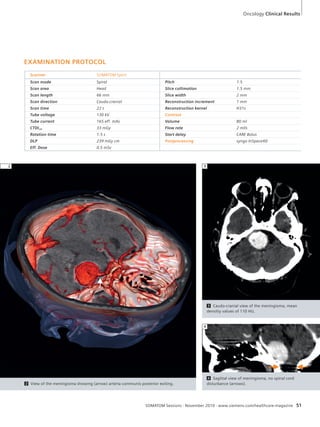

from the start,” says Abdala. “We

had already had excellent previous expe-riences

with devices produced by Sie-mens.

The cost was pretty reasonable,

even low, one could say, if you take into

account the standard in the market. And

both speed and spatiotemporal resolution

were very good.” UMDI is now building

its first hospital, with the intention of

keeping its main focus on diagnosis

while also targeting some treatments.

According to Abdala, the SOMATOM

Spirit was instrumental in helping the

clinic to take this next step.

“I have already recommended the Spirit

to five or six small hospitals with which

we have been in touch,” he says. “It is

ideally adapted to clinics that are start-ing

up. If you’re not sure about how big

your demand for exams is going to be, it

is a great machine for routine work. You